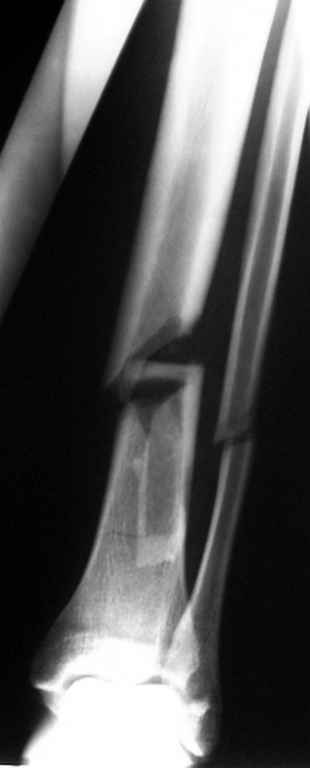

Уважаемые коллеги! Хотел-бы услышать Ваше мнение по поводу того, кто как относится к наличию свободных осколков в линии перелома и чем при этом руководствуется - размер, локализация, возраст и т.д.

Консультировал рентгенограммы после интрамедуллярного остеосинтеза бедра гвоздем Fixion. Пациенту объяснили, что важнее сохранить перелом "закрытым" чем фиксировать осколок из дополнительного разреза. Сами собираемся оперировать голень и думаем, что без "открытия" места перелома не обойтись.